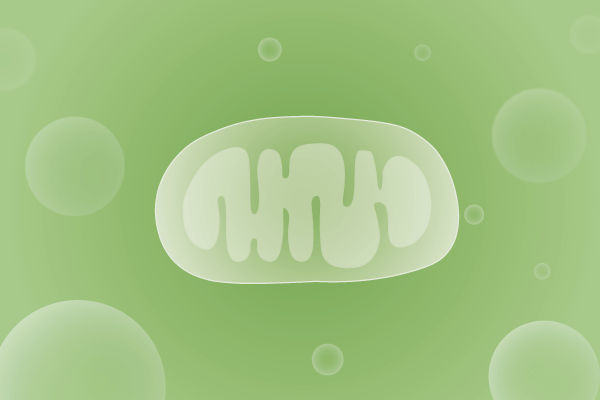

线粒体疾病

线粒体病是因遗传缺陷引起线粒体功能障碍,导致 ATP 合成下降、能量产生不足,可导致临床多系统受累的一组疾病。可单独或同时累及神经、肌肉、眼、耳、消化、内分泌、心血管、肾脏及血液系统等。线粒体病从新生儿到成年期均可发病,发病率约为1/8500。

了解详情 >